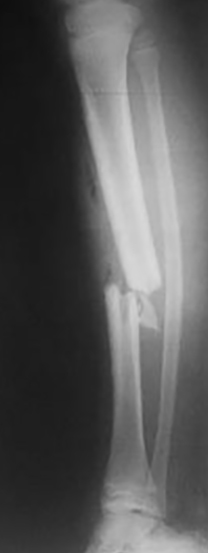

Del total de pacientes, cuatro tuvieron resultados excelentes y cuatro satisfactorios. Todas la fracturas consolidaron en un tiempo medio de 15 semanas (rango: 12-21). Se realizó solo aporte de injerto de esponjosa en un paciente con una pseudoartrosis atrófica tratada previamente con EEF. Todos los pacientes presentaron una movilidad completa de la rodilla y cuello de pie indolora, sin manifestar alteraciones de la marcha y no se encontraron deformidades angulares (mediante examen clínico y radiografías) ni discrepancias en los miembros inferiores significativas con un promedio de hipercrecimiento de 1,6 (rango: -5 a 10) mm. Se autorizó el apoyo parcial a las 5 semanas (rango: 4-8 semanas) y el apoyo total a las 10 (rango: 8 – 13) semanas. Como complicaciones menores, cuatro pacientes presentaron dolor en el implante, sobre todo en aquellos pacientes donde se colocó la placa en el sector interno y en la configuración externa / anterior, sin significado funcional, coordinándose para retirar las mismas (Tabla 1) (Tabla 2) (Figura 1) (Figura 2).